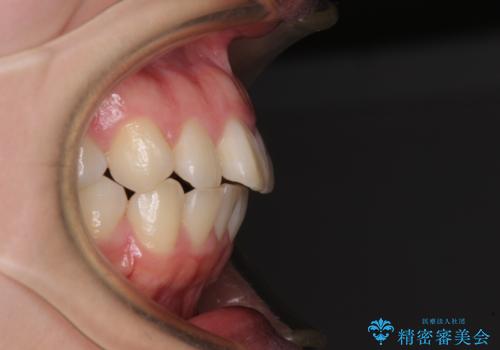

- 口元の突出感を気にして来院された患者様です。

口元を積極的に引っ込めるために、上下左右の第一小臼歯を4本抜歯することとし、ワイヤー装置による矯正治療を行うこととしました。

上下前歯がくちばしのように突出していましたが、抜歯矯正により口元が引っ込み、唇が閉じやすくなり、鼻の下の膨れた感じも解消されました。